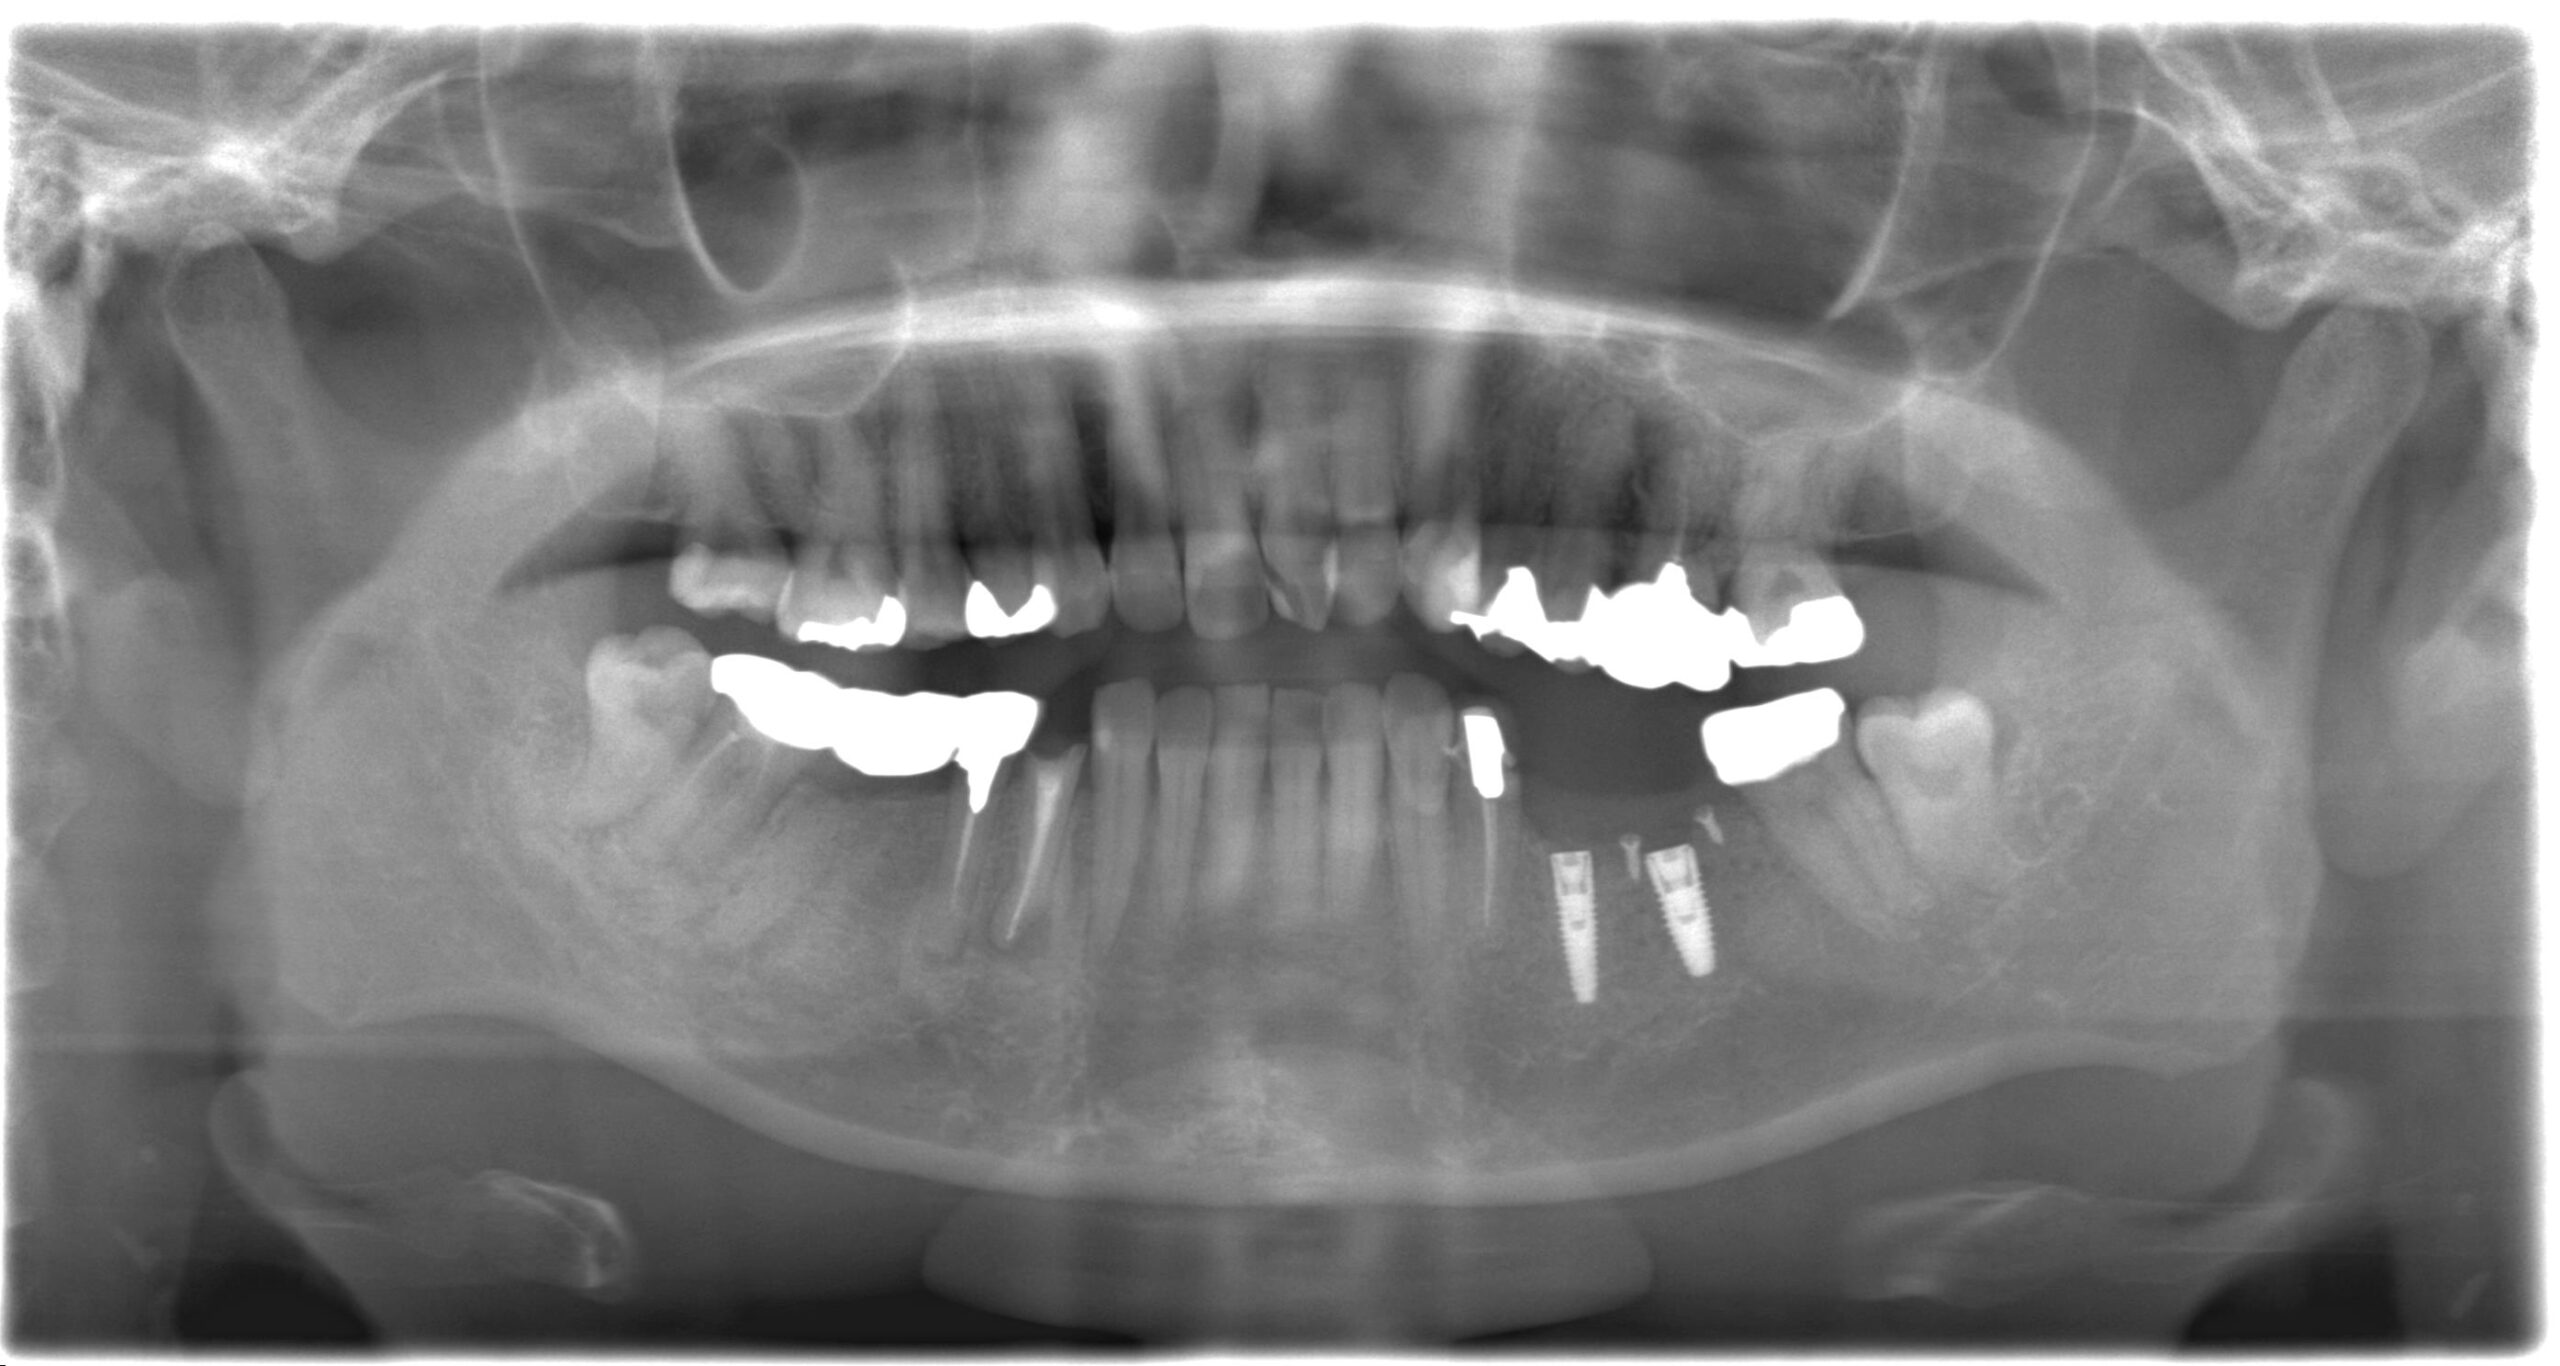

症例03

60代 女性 奥歯を失いよく噛めない

術後レントゲン

| 主訴 | 歯がないところをしっかりと治し、将来の不安をなくしていきたい。 |

| 年代・性別 | 60代 女性 |

| 治療部位 | 下顎5~6 |

| 治療費用 | インプラント手術料 300,000円×2=600,000円 骨造成料 50,000円 筋肉内鎮静法 30,000円 セラミック上部 120,000円×2=240,000円 |

| 手術回数 | 1回 |

| 治療期間 | 3ヶ月 |

| 手術時間 | 1時間 |

| 治療回数 | 4回 |